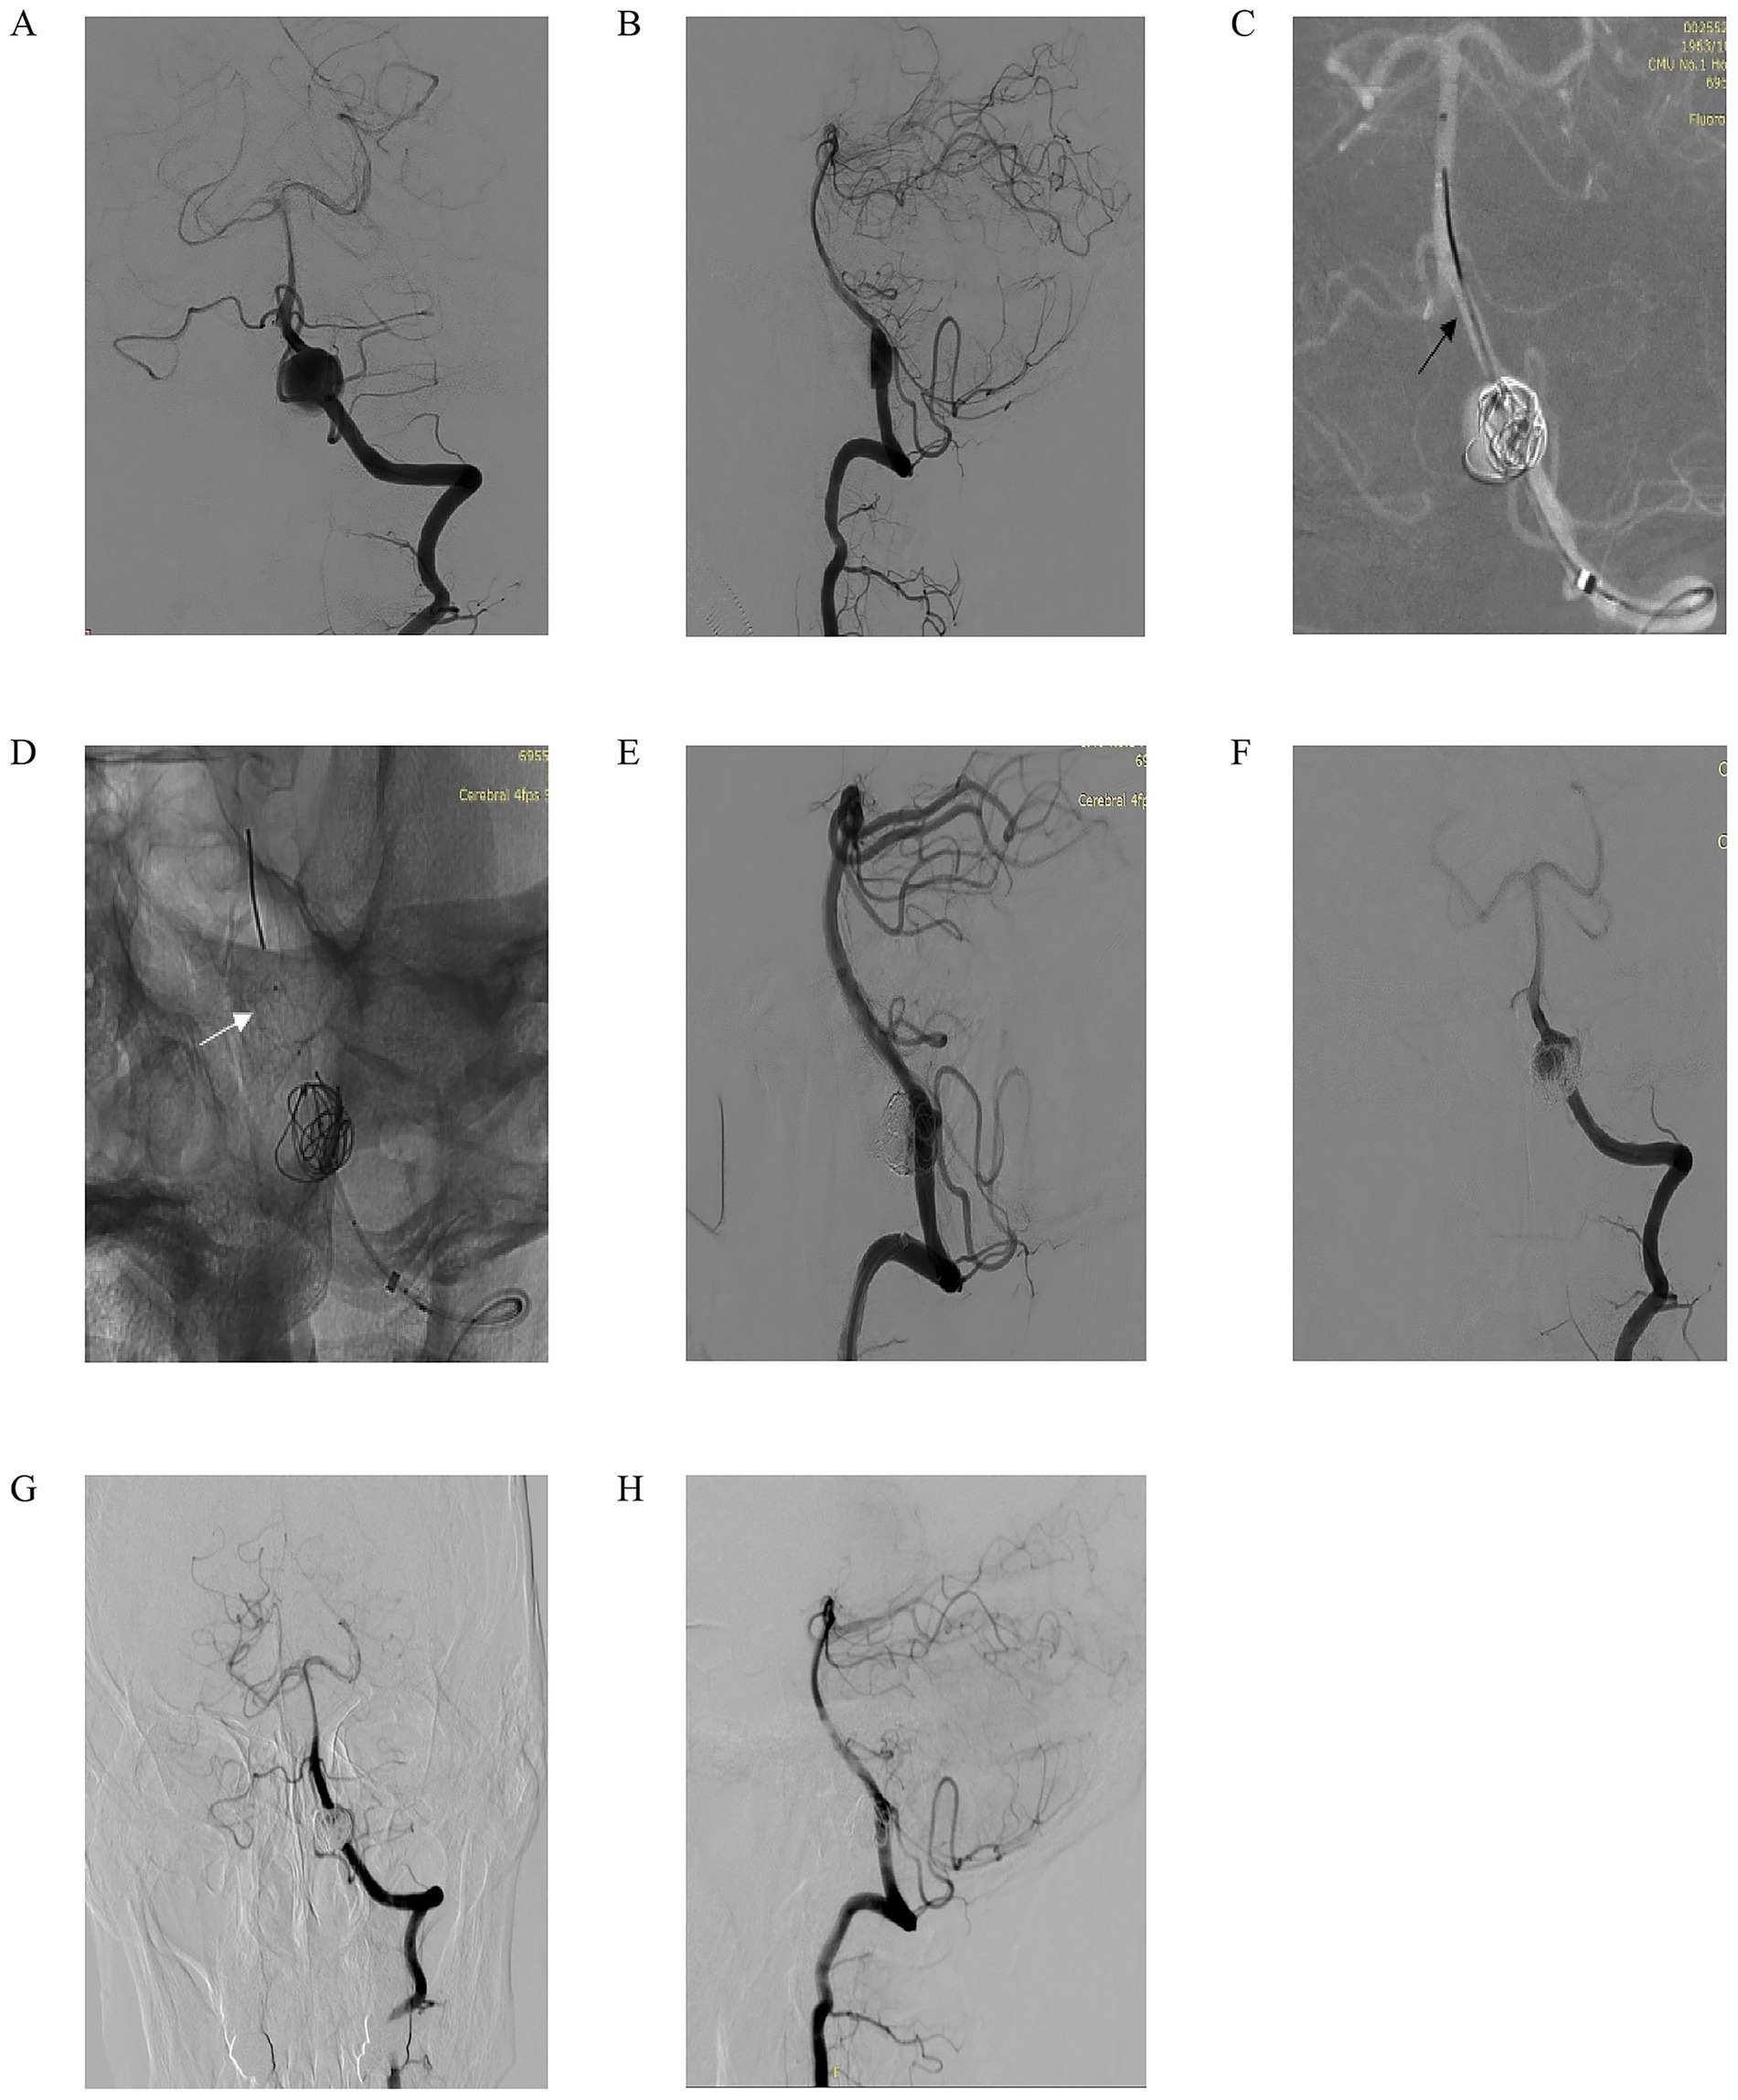

We present another case of a 60-year-old woman who presented with intermittent headaches for 2 months, without nausea, vomiting, or dysphagia. Computed tomography angiography (CTA) revealed a left vertebral artery V4 segment aneurysm, and neurological examination showed no focal deficits. Left vertebral artery DSA in anteroposterior and lateral views (Figures 3A,B) confirmed a fusiform aneurysm at the V4 segment. Under working-angle roadmap guidance (Figure 3C), a 6F intermediate catheter and microcatheter XT27 were navigated to the target site, with the Lattice FD-MB positioned distally (black arrow marks the deployment landmark). Partial coiling of the aneurysm sac was performed, while the Lattice FD-MB remained in a semi-deployed state (Figure 3D, white arrow highlights optimal distal expansion of the device). Post-coiling DSA (Figures 3E,F) demonstrated substantial aneurysm filling with coils, stable expansion of the Lattice FD-MB, preserved hemodynamics, and unimpaired flow in the left posterior inferior cerebellar artery (PICA). At the 7-month follow-up, DSA (Figures 3G,H) confirmed complete aneurysm occlusion and patency of the parent vessel without stenosis and maintained PICA perfusion. This case highlights the efficacy of combining flow diversion and coiling in managing complex fusiform V4 aneurysms, achieving durable occlusion while protecting critical branch vessels.

Figure 3. A 60-year-old man intermittently experienced headaches for 2 months. There was no nausea or vomiting, and no choking while drinking water. Computed tomography angiography (CTA) indicated an aneurysm in the left V4 segment. No positive signs were found in the specialized physical examination. (A,B) Left vertebral artery DSA in anteroposterior (A) and lateral (B) views confirming the presence of a fusiform aneurysm at the V4 segment; (C) Working-angle roadmap guidance for navigation of a 6F intermediate catheter and microcatheter (XT-27) to the target site. The black arrow marks the distal deployment landmark of the Lattice FD-MB; (D) Partial coiling of the aneurysm sac with the Lattice FD-MB maintained in a semi-deployed state. The white arrow highlights the optimal distal expansion of the device; (E,F) Post-coiling DSA in anteroposterior (E) and lateral (F) views demonstrating substantial aneurysm filling with coils, stable expansion of the Lattice FD-MB, preserved hemodynamics, and unimpaired flow into the left posterior inferior cerebellar artery (PICA); (G,H) Seven-month follow-up DSA in anteroposterior (G) and lateral (H) views confirming complete aneurysm occlusion, patency of the parent vessel without stenosis, and maintained perfusion of the PICA.